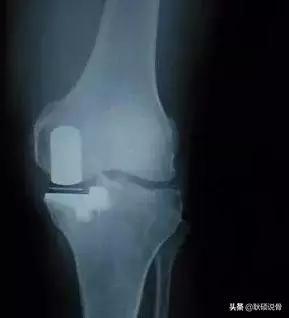

第三种,单髁置换术(UKA)。适用于关节内畸形,而周围软组织韧带等结构没有破坏。这种置换理念如今被越来越多的专家认可。因为只置换了1/3的关节面,可以保留交叉韧带、内测副韧带、外侧副韧带。术后回归自然状态。也就是说患者术后是靠自身韧带的引导进行膝关节活动。

第四种,全膝关节置换术(TKA),对于严重膝关节骨刺,严重影响生活的,这种方式缓解疼痛的效果显著,可以一次性解决已经发生畸形的膝关节,随着膝关节生存率越来越高,术后在疼痛、关节功能及活动度等方面均有明显的改善,极大地提高病人的生活质量,以及TKA手术技术的日渐成熟,如今已经成为国际国内治疗膝关节骨性关节炎最流行的骨科手术。